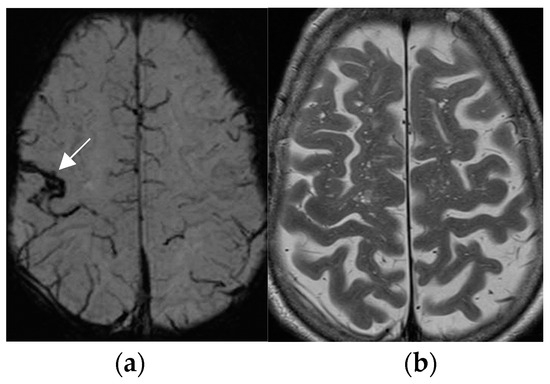

Postsurgical pathologic analysis of specimens of lesions missed by a negative brain MRI—even when performed using an epilepsy specific protocol—disclosed focal cortical dysplasia (FCD), hamartia, gliosis, and hippocampal sclerosis as the most common entities (Figure 1) [62].

Histologically confirmed FCD I depicted by abnormal deep and straight left. collateral sulcus with a slight blurring of the gray–white matter junction on the FLAIR image. (a) (1.7 mm) and signal hyperintensity of the cortical border. Reduction of adjacent parahippocampal white matter (white arrow on MP2RAGE sequence) (b) slice thickness 0.9 mm. The hippocampus displays a mild signal increase on the FLAIR image (without atrophy) as a sign of dual pathology. Both lesions were missed on prior 1.5 T examination in a patient with left temporal lobe epilepsy.

4.2. A Standardized Epilepsy Specific Protocol Provides Superior Diagnostic Yield

A comprehensive epilepsy-targeted MRI protocol is the key factor to identify, localize, and characterize an epileptogenic lesion (Figure 1). The neuroimaging task force of the ILAE advises the “Harmonized Neuroimaging of Epilepsy Structural Sequences” (HARNESS-MRI) protocol that encompasses three “core” sequences: iso-tropic submillimetric FLAIR and 3D T1 images and high-resolution 2D T2 sequences to be performed soon after the first seizure [64].